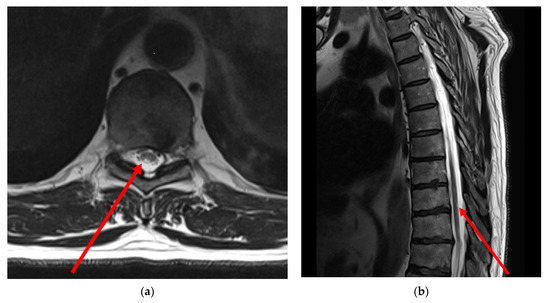

- Thoracic MRI: T2-weighted MRI images of the thoracic spine showed asymmetrical mild patchy high-signal changes in the spinal cord between levels D9 and D10, affecting the posterolateral sides of the spinal cord bilaterally, but predominantly on the right side with minimal swelling (Figure 1).